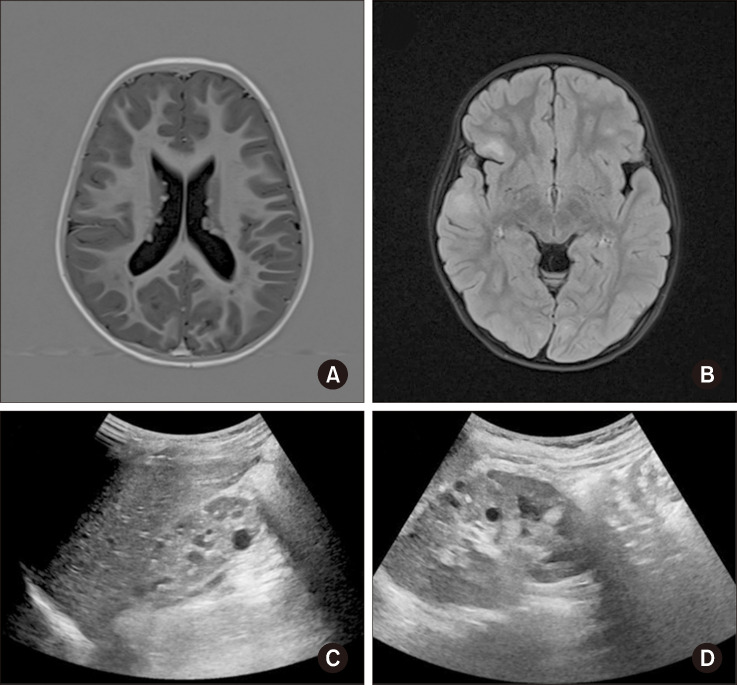

Tuberous Sclerosis Complex Caused by TSC2 Inversion and Deletions Identified Using Whole-genome Sequencing: A Case Study.